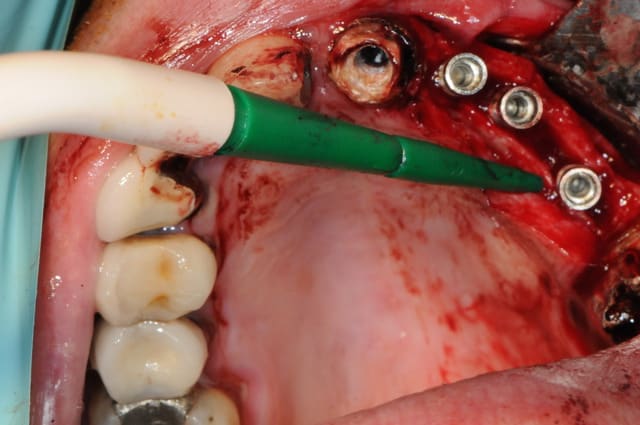

Mise en application du cours +TP

chez le Dr. Sp... à Mulhouse

coaching de Pxav, pour l'AD et photo de D57, mon maitre...

que du plaisir d'assister un confrère qui a tout compris et qui voulait simplement une mise en condition pour vérifier ses capacités.

25/02/2011 à 21h41

c'est vrai que pxav était fortement intéressé par les assistantes...

mais bon en bon pro qu'il est, il a tout de même été très attentif à ce qu'il faisait.

c'était une belle chir.

sans cette intervention il ne restait pas d'autre alternative qu'une greffe de grande étendue.

en plus on a rétabli un volume vestibulaire très satisfaisant.

merci Olivier, le résultat était vraiment sympa, petite fissure sur la canine, mais SPie.... a pratiquement recrée une courbure similaire au coté opposé,. pratiquement uniquement guidé oralement, mis à part les "pressions" sur les mains de l'AD pour lui faire sentir les axes à donner aux ostéotomes.

le Split a été comblé avec des particules d'os prélevées sur la BM au scraper et PRF par dessus.